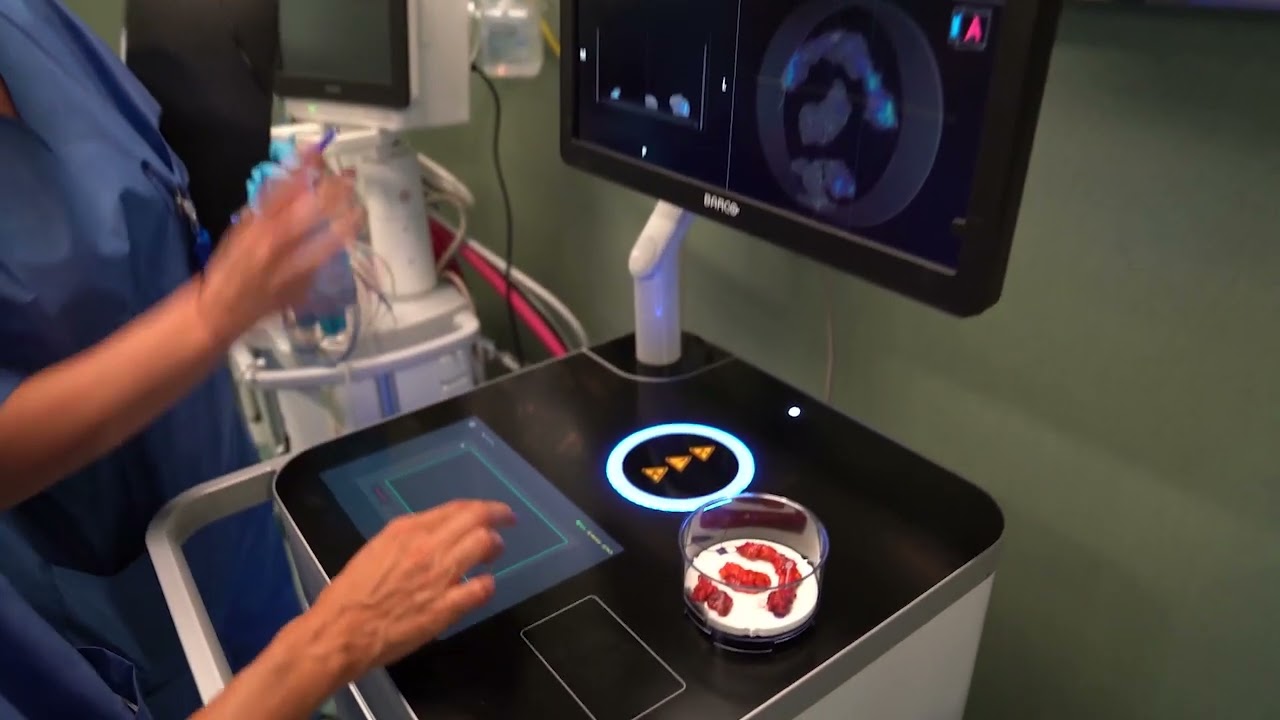

#353 Robot assisted 3D models-guided ureteral reimplantation- Dr.Federico Lavagno

KS Awards, Robotics, Surgeon ';